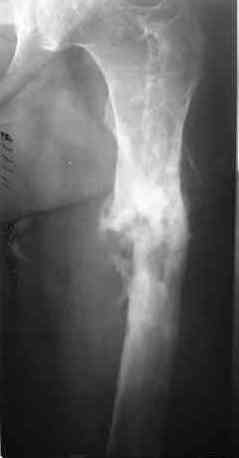

Через 1 год и 7 месяцев после травмы у больного диагностированы ложный сустав и хронический остеомиелит левой бедренной кости. Произведено удаление металлических фиксаторов, секвестрэктомия и остеосинтез бедренной кости внешним двухплоскостным стержневым аппаратом [image 03, 04] .

Через 3 года после травмы констатировало отсутствие консолидации бедренной кости, сохранение признаков хронического остеомиелита (свищ в нижней трети левого бедра). Произведен демонтаж аппарата, реостеосинтез бедренной кости спице-стержневым аппаратом, некрсеквестрэктомия. В аппарате удалось лишь частично произвести устранение углообразной деформации бедренной кости [image 05] .

Через 4,5 лет после травмы выявлены рентгенологические признаки консолидации перелома, признаки хронического остеомиелита купировались. Аппарат был демонтирован. Пациент продолжил ходьбу с дозированной нагрузкой на конечность при помощи костылей. Через 2 месяца начал ходить при помощи трости. Однако, еще через 2 месяца отметил появление свищей на бедре с гнойным отделяемым и укорочение длины конечности.